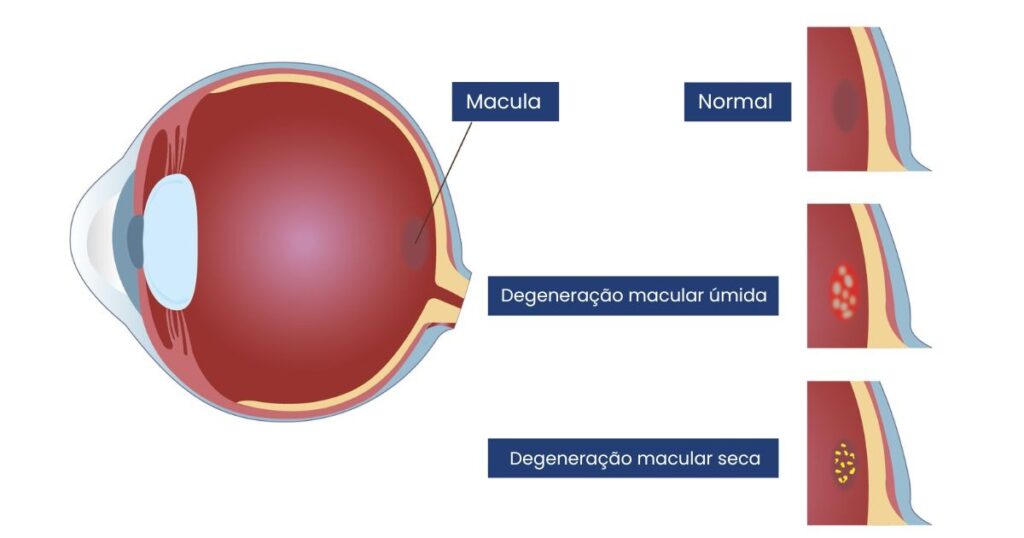

A DMRI é uma doença degenerativa que atinge a mácula. Ela ocorre principalmente devido ao envelhecimento das células responsáveis pela visão central e das estruturas que as sustentam.

Ao longo dos anos, resíduos metabólicos acumulam-se sob a retina, prejudicando a nutrição local. Em alguns casos, novos vasos sanguíneos anormais tentam se formar para compensar a falta de oxigênio, e é aí que surgem os maiores problemas.

Tipos de Degeneração Macular Relacionada à Idade (DMRI)

A DMRI é dividida em duas formas principais, cada uma com impactos e tratamentos diferentes:

1. DMRI seca (ou atrófica)

É a forma mais comum, representando cerca de 85–90% dos casos. Ocorre quando há um desgaste progressivo das células da mácula (atrofia), resultando em visão borrada e perda gradual da nitidez.

- Relacionada ao acúmulo de drusas (depósitos amarelados sob a retina)

2. DMRI úmida (ou exsudativa)

É a forma menos comum, porém mais agressiva. Caracteriza-se pelo surgimento de vasos sanguíneos anormais sob a retina (neovascularização). Esses vasos são frágeis e costumam vazar sangue e líquido, causando perda rápida da visão central.